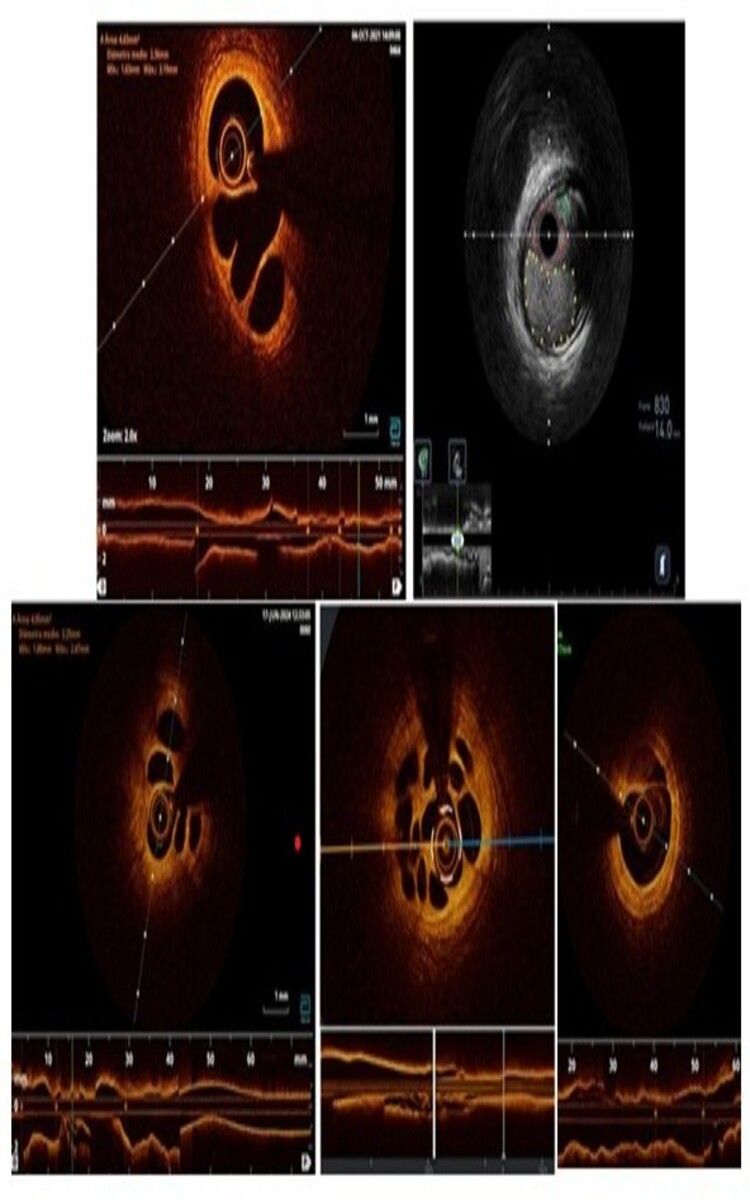

Resultados: Serie de 5 casos (4 varones (80%), edad media 58 ± 12), remitidos por SCACEST (3 casos), SCASEST y ángor estable. En 2 casos la arteria con RETC era el vaso responsable y en 3 casos no lo era. En 4 casos se confirmó la presencia de RECT mediante OCT y en 1 mediante IVUS (imposibilidad de obtener imágenes de calidad con OCT al ser oclusiva para el contraste). Se realizó medición de la repercusión funcional de la lesión con flujo de reserva fraccional (FFR) en 4 casos y en 1 con la relación de flujo de ciclo completo (RFR) por hiperreactividad bronquial del paciente. Se documentó la repercusión funcional de todas las lesiones, que a continuación fueron tratadas con stents farmacoactivos, con buen resultado angiográfico y funcional (se repitieron las pruebas de evaluación de isquemia tras el stent) en todos los casos.

Prueba de imagen diagnóstica típica de recanalización espontánea de cada caso (en orden de izquierda a derecha y de arriba a abajo).